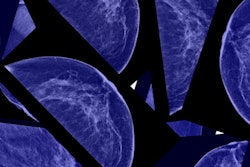

An act making mammograms more accessible in Illinois is now in lawmakers’ hands. House Bill 4180 (HB 4180), introduced October 23, 2023, includes several instances of new and specific provisions, such as the following:

- Coverage for certain types of mammography shall be made available to patients of a specified age (rather than only women of a specified age).

- Coverage for molecular breast imaging will be required and, in those cases where it is not already covered, breast MRI will also be covered.